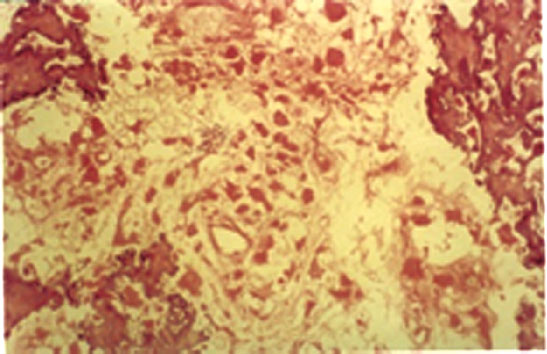

与其他保肢治疗方案相比,HIFU消融治疗是将肿瘤“切除”和肢体重建融为一体的非侵入性保肢治疗措施。HIFU消融治疗骨肿瘤的基础是肿瘤对骨组织破坏使其透声性增加,适当频率的高强度聚焦超声束易于穿过骨组织。HIFU消融治疗能使骨内外的肿瘤组织发生凝固性坏死(图5-1、图5-2),即“热切除”肿瘤,同时利用原位灭活肿瘤骨段进行肢体重建,达到非侵入性保肢治疗根治原发性恶性骨肿瘤的目的。对于不能根治的部分原发性恶性骨肿瘤和转移性骨肿瘤患者,以减瘤负荷为目的,可以缓解症状、改善生存质量、延长生存期。

图5-1 兔VX2恶性骨肿瘤治疗后病理组织学变化

左图.治疗后见骨内外肿瘤组织发生凝固性坏死,其边缘有明显的充血带;右图.光镜下见治疗区内组织疏松,肿瘤细胞核固缩、核碎裂,治疗区与非治疗区分界清楚

图5-2 人骨肉瘤治疗3周后见肿瘤细胞核消失,仅残留细胞轮廓